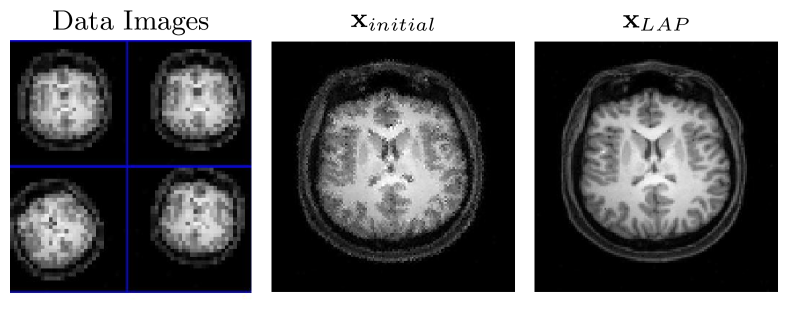

We compare results for the methods using the relative errors of the resultant image and motion parameters. We separate relative errors for the image and motion. Plots of these errors against iteration can be seen in Fig. 2 for the problem with % added noise. The corresponding resulting image for LAP for the % error case can be seen in Fig. 1. Lastly, a table of relevant values including the average number of iterations, minimum errors for image and motion, matrix-vector multiplications, and CPU timings for the methods taken over different realizations of the problem for all three noise levels is in Table 1.

For direct regularization using the discrete gradient operator, the solutions for all three methods are comparable in terms of the relative error for the motion, with LAP and BCD slightly outperforming VarPro for the relative error of the recovered images. This is a direct result of the element-wise bound constraints on the resultant images using these methods. Furthermore, these solutions are superior to those for all three methods using hybrid regularization or the identity operator, suggesting that this is a more appropriate regularizer for this problem. LAP with the discrete gradient operator recovers the most accurate reconstructed image of the three methods and achieves better or comparable recovery of the motion parameters. This is observable in the relative error plots for the % added noise case in Fig. 2, and for the problem with all three noise levels in Table 1. We can also see from the relative error plots that LAP tends to recover the correct motion parameters earlier in the Gauss–Newton iterations than either BCD or VarPro. In terms of method cost, both the LAP and BCD iterations cost significantly less in terms of time and matrix-vector multiplications than those of VarPro, resulting in faster CPU times and fewer matrix-vector multiplies for the entire optimization. However, while BCD is also relatively cheap in terms of matrix-vector multiplies and CPU time, LAP outperforms it in terms of solution quality. Overall, the LAP approach compares favorably to VarPro and BCD for this example in terms of both the resulting solutions and cost, outperforming both methods.